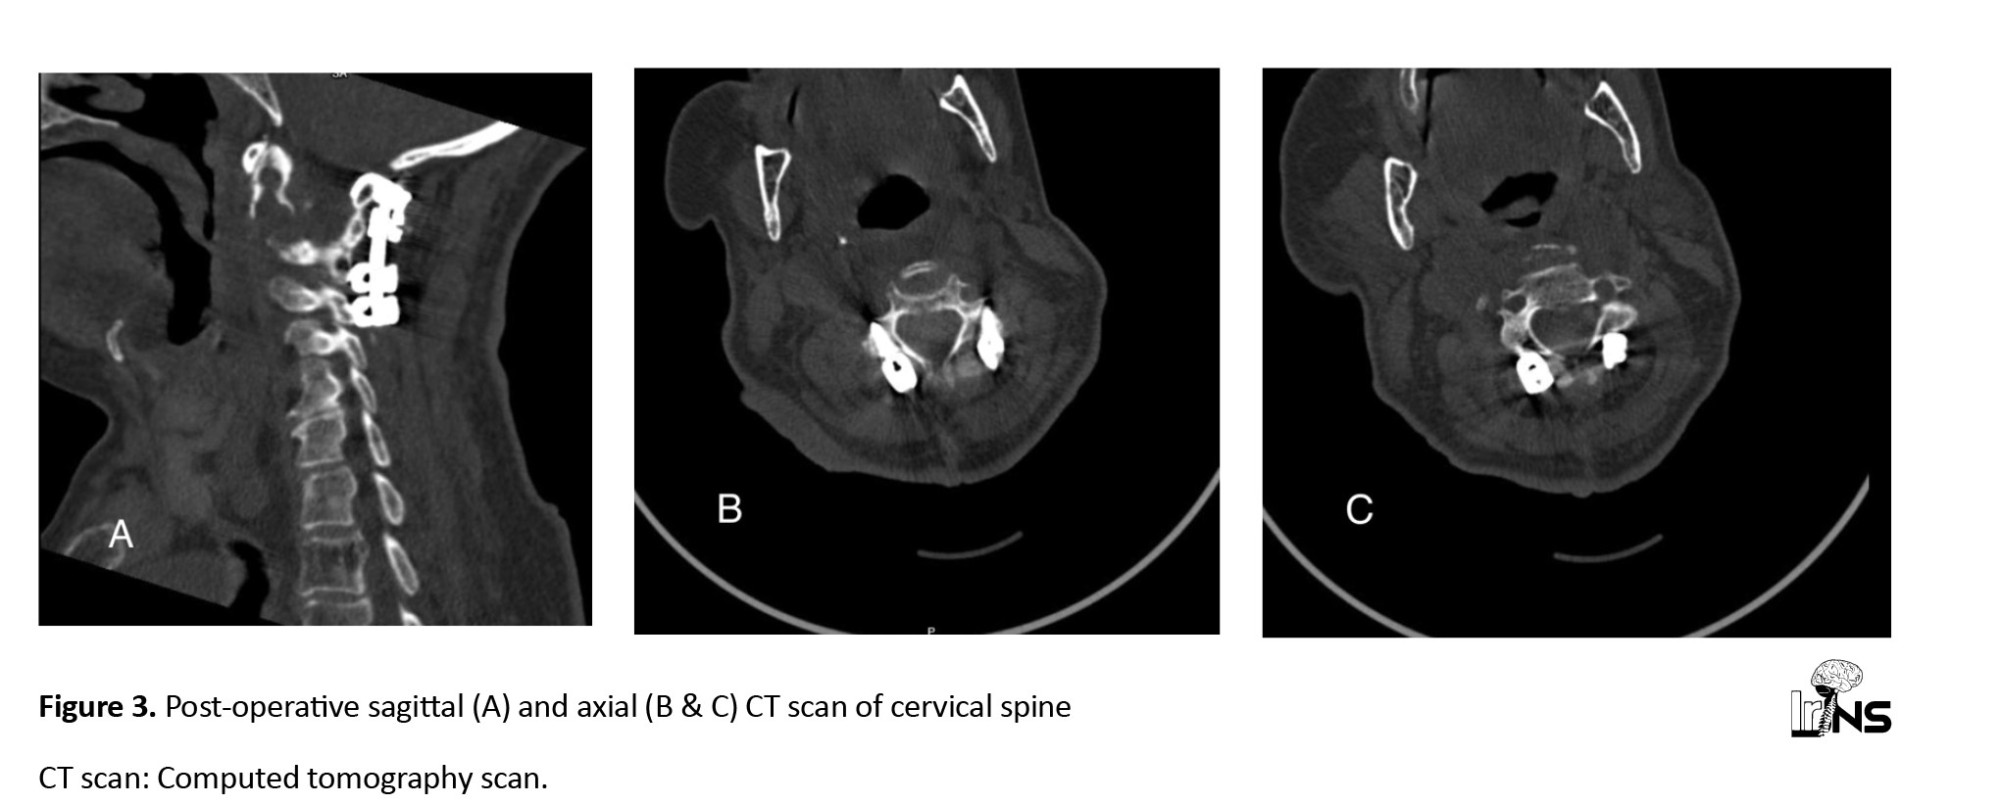

Given the symptoms, patient age, and structural instability of the craniospinal junction with the lytic C2 lesion, we decided to perform posterior cervical fusion with three main objectives: To improve the clinical symptoms, stabilize the cervical spine, and prevent devastating neurological consequences. Surgery was performed under general anesthesia and neurophysiological monitoring. The patient was premedicated with intravenous antibiotics (2 g of sodium cefazolin). The patient was placed in the prone position with an adequate cushion, and his head was fixed using a Mayfield clamp under general anesthesia. After division of the skin and posterior neck muscles, the Laminar hook on the C1 and C3-C4 lateral mass was inserted. An additional posterior transpedicular biopsy of the bone marrow was performed using the Jamshidi needle. Within 1 d postoperatively, the patient’s pain resolved without new neurological deficits, and a CT scan confirmed cervical stability (

Figure 3).

Moreover, the fragile outer borders of the C2 body pose a significant fracture risk, with potentially catastrophic consequences. Single-session posterior cervical fixation is rarely recommended for treating metastatic cervical instability. To our knowledge, the transpedicular approach to access the C2 body is not a safe option due to the vertebral arteries’ proximity and the axis pedicles’ small size [3]. The transoral approach provides the most straightforward access, offering the advantage of a short distance to the C2 vertebral body, thereby minimizing the risk of injury to crucial vascular structures [13, 14]. However, we decided against a second surgery with a higher risk of infection and bleeding due to the undiagnosed nature of the lesion. Therefore, posterior transpedicular biopsy via a Jamshidi needle was the optimal option for confirming the diagnosis of SBP. The posterior approach also allowed stabilization of the craniocervical junction. After careful consideration, the posterior approach was selected, and C1 laminar hooks with C3-C4 lateral mass fixation were performed along with C2 transpedicular biopsy.